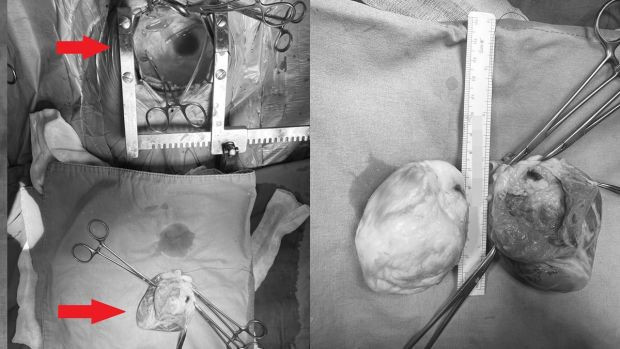

8 saat süren ameliyat sırasında Ekin Ada'nın kalbini "yerinden söküp" tümörü ameliyat masasında temizlendikten sonra tekrar nakledildi.

Tümörün içinden hayati bir damarın geçmesi nedeniyle kalp yerindeyken ameliyat etmenin imkansız olduğunu anlatan Prof. Dr. Kalangos, çok büyük bir riske girerek kalbi yerinden çıkarıp ameliyat etme yolunu seçtiklerini vurguladı.

Prof. Dr. Kalangos, "Çok dikkatli çalışmamız gerekiyordu o nedenle kalbi yerinden söktük, damarlarından ayırdık ve masanın üzerine yatırarak (kalp vücuttan ayrıyken) ameliyata devam ettik. Göğüs boşluğu tamamıyla boş kaldı, 'kalpsiz' bir durumda makineye bağlı takip edildi. Kalbi masanın üzerinde sol karıncığa hasar vermeden, hem kasları hem arterleri koruyarak açtık. Dr. Yılmaz Zorman ile beraber nefesimizi tuttuk, ince ince, soğan kabuğu soyar gibi kalp kasından tümörü ayırdık. Tümörün içinden geçen o ince, bir milimetrelik koroner damarı bulduk ve onu da titiz bir şekilde tümörden ayırarak kalbi tamamen temizledik. Onarılmış kalbi tekrar yerine taktık" dedi.